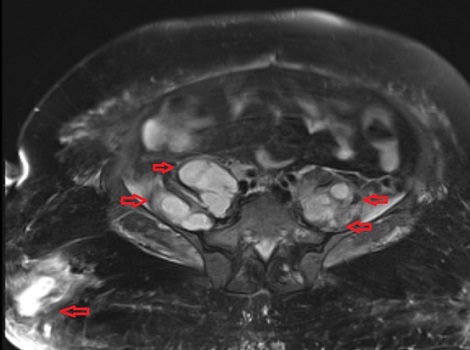

Στις εικόνες της μαγνητικής διακρίνονται τα διάφορα αποστήματα (κόκκινα βέλη) στους μύες (λαγνοψωίτες, απιοειδείς και δεξιό γλουτιαίο).

Το απόστημα του δεξιού λαγονοψωίτη καταλάμβανε ολόκληρη την έκταση του μυός. Τέλος, σημαντικό νέο εύρημα ήταν η παρουσία επισκληρίδιου εμπυήματος το οποίο κρίθηκε ότι δεν χρειάζεται χειρουργείο.